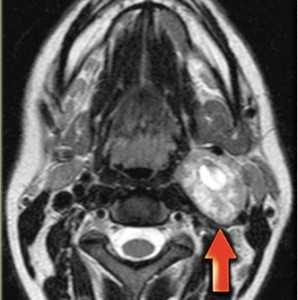

(Слева) МРТ Т1ВИ FS с КУ, аксиальная проекция. Крупная шваннома в нижней части шеи справа, которая лежит на средней лестничной мышце. Отмечается неравномерное накопление контраста по периферии опухоли. Центральная область, не накапливающая контраст, представляет собой участок кистозной дегенерации. При поражении нижних шейных лимфоузлов патологический очаг обычно расположен медиальнее, возле внутренней яремной вены.

(Справа) MPT Т2ВИ, аксиальная проекция. В нижней части шеи визуализируется шваннома сигнал гетерогенный гиперинтенсивный. Опухоль, расположенная в паравертебральном пространстве, раздвигает и деформирует переднюю и среднюю лестничные мышцы.